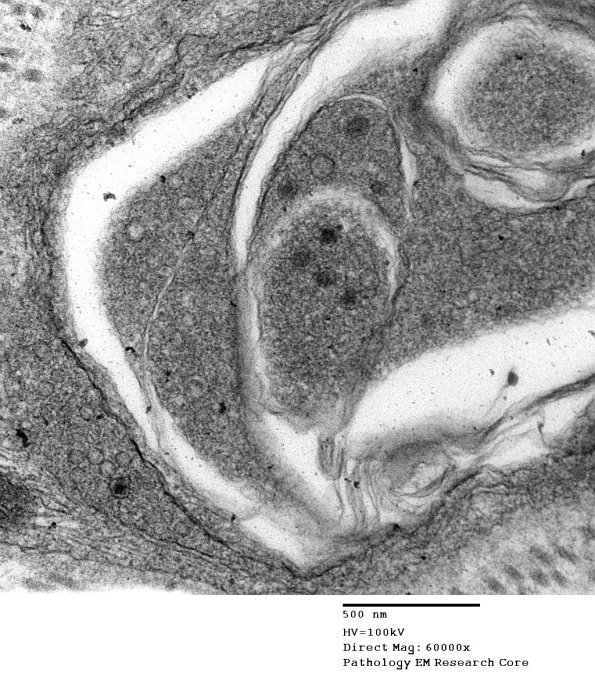

Several magnifications of an axon demonstrate a complex appearance with prominent pale clefts and a few dense core vesicles. (electron micrographs)